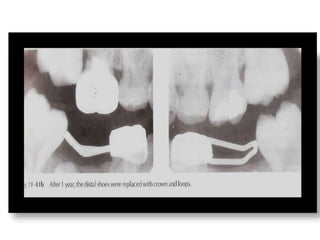

Distal Shoe

• Should be evaluated with

radiograph prior to

cementation

– Length

– Position

• Will be replaced with

another space maintainer

when permanent teeth

erupt.

Distal Shoe • Shouldbe evaluated with radiograph prior to cementation – Length – Position • Will be replaced with another space maintainer when permanent teeth erupt.